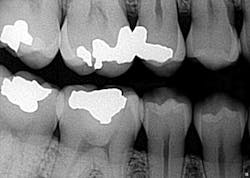

This was the first question out of my patient’s mouth when I diagnosed him with a cavity at his new patient exam. Of course he had to ask … his last filling was when he was 14 (he is now 37), and understandably there was an underlying tone of doubt in his voice. After all, what dentist in his or her right mind would look at tooth No. 29 and say, “That’s a cavity”? (Figs. 1 and 2)

Fig. 1

In dental school, we were taught to rely on a sharp explorer and sharp eyes to diagnose caries. Upon initial examination, I did not consider this to be a cavity. If we can’t see it, it’s not there, right? Why doubt what we were taught? The answer is simple. Because we can’t SEE everything that needs to be diagnosed, we therefore need to utilize adjunct diagnostic tools to be sure we are thorough in our examinations.